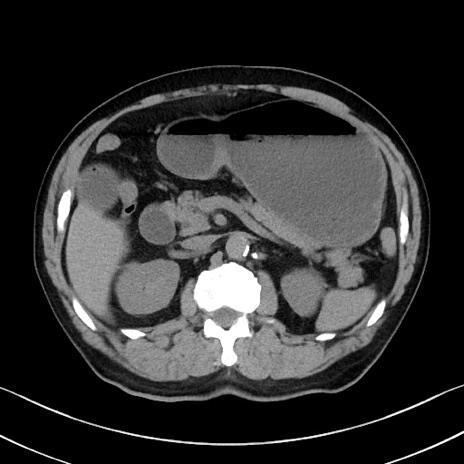

症例35(横断像)

【症例】70歳代 男性

【主訴】腹部膨満、嘔吐

【現病歴】昨日より腹部膨満感出現。本日増悪し、仙痛出現。嘔吐あり、受診。

【既往歴】糖尿病、胆摘後

【身体所見】BP 149/80mmHg、HR 74/min、BT 35.9℃、腹部:膨満、軟、圧痛なし。腸雑音減弱あり。上腹部正中切開瘢痕あり。

【データ】WBC 13500、CRP 1.72